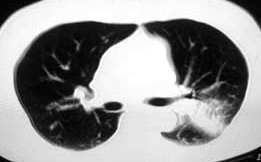

以下是引用ysxyy在2006-3-4 20:19:00的发言:[br]首先考虑炎症,tb暂不考虑;[br]理由:1、病变范围局限在左上肺尖后段,界限较清;[br]2、病史:青壮年34岁,以咳嗽、发热就诊,急性起病;[br]3、

以下是引用lkc8963在2006-3-4 21:27:00的发言:[br][quote]以下是引用ysxyy在2006-3-4 20:19:00的发言:[br]首先考虑炎症,tb暂不考虑;[br]理由:1、病变范围局限在左上肺尖后段,界限较清;[br]2、病史:青壮年34岁,以咳嗽、发热就诊,急性起病;[br]3、